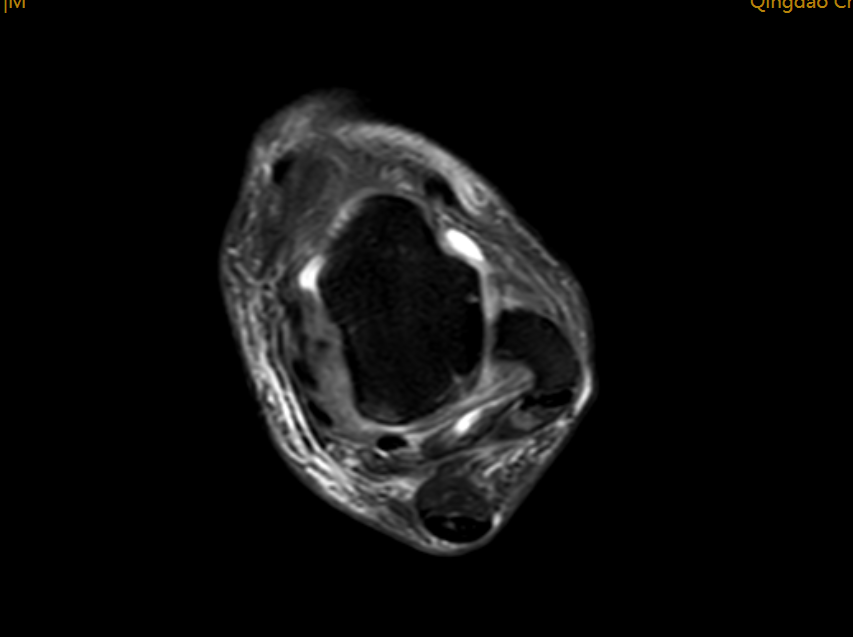

术前完善踝关节MRI示距腓前韧带(ATFL)损伤部位的T2加权磁共振成像:斜轴位。正常情况下,ATFL的纤维呈一束低信号区域,但此图像显示ATFL不规则且在距骨侧有分离(箭头)